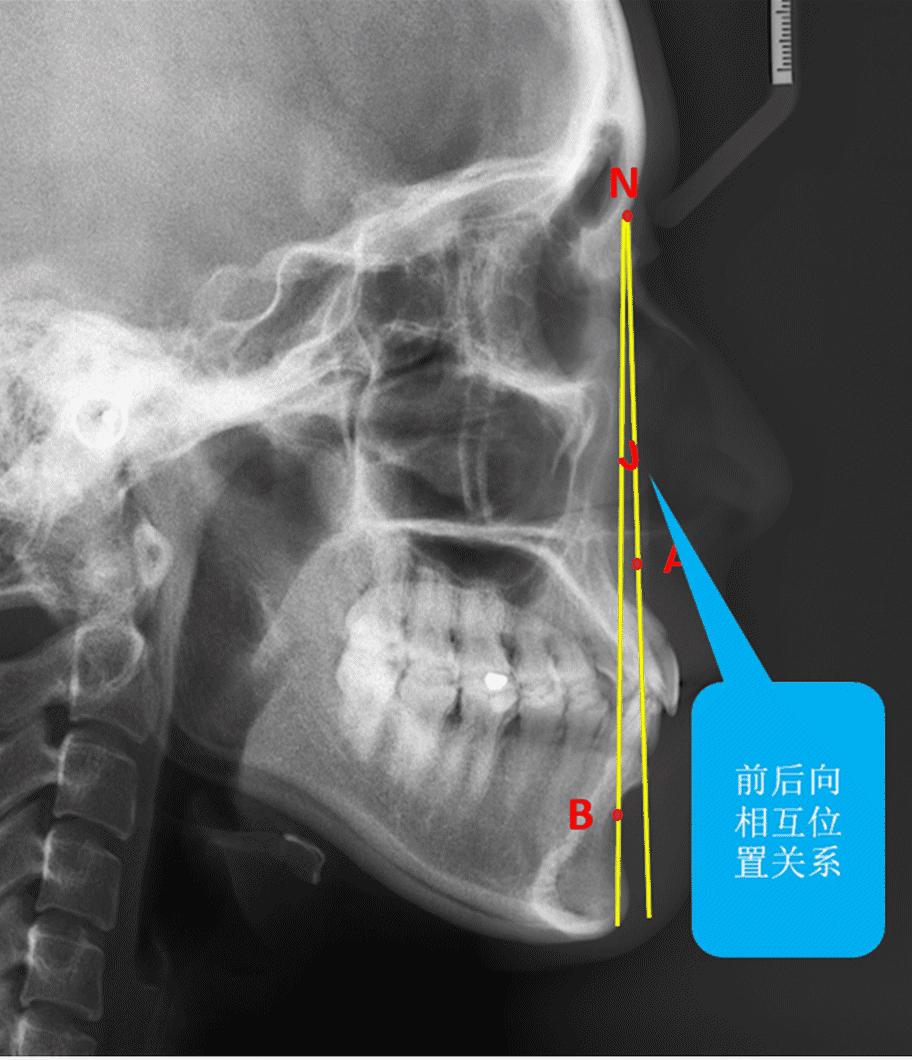

再好的医生也通过X光片,通过头影测量,协助判断:你骨性还是牙性?正畸是否能解决你的问题?你牙齿“错”在哪里?"错"了多少?以及预测牙齿矫正后的变化。

正畸医生要综合无数指标来判断骨性牙性,小编只是放出了其中一小个供参考的角度。通过头颅侧位片来观察颅骨、颌骨的长、宽、高发育情况,并进行许多测量分析即"透过现象看本质","深入内部"的检查,依次做出的诊断才更全面、更可靠,此后医生的治疗才会胸有成竹。